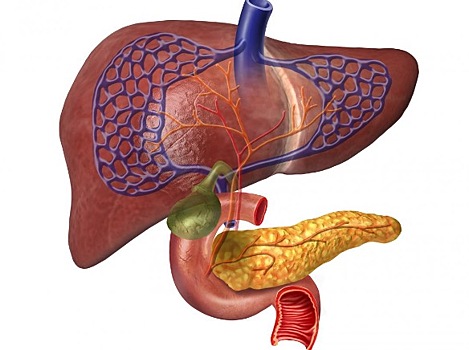

Дисфункция сфинктера Одди является редким состоянием пищеварительной системы. Дисфункция происходит, когда сфинктер Одди не открывается и не закрывается должным образом. Это может произойти по многим причинам, таким как: фиброз; воспаление; анатомические аномалии; спазмы. Дисфункция сфинктера Одди вызывает накопление пищеварительных жидкостей в поджелудочной железе и печени, что приводит к интенсивному болевому синдрому в животе. Поджелудочная железа производит поджелудочный сок, а в печени вырабатывается желчь, которая представляет собой химические вещества, помогающие переваривать пищу в кишечнике. Обычно они попадают в тонкий кишечник через проток, который открывается и закрывается мышцей, называемой сфинктером Одди. Дисфункция сфинктера Одди может вызвать: холецистит; панкреатит. Дисфункция сфинктера Одди — симптомы Люди с дисфункцией сфинктера Одди обычно испытывают сильную боль в животе. Боль может быть повторяющейся и меняться по интенсивности. Другие симптомы могут включать: диарею; лихорадку; тошноту; рвоту; потерю аппетита; снижение веса. Дисфункция сфинктера Одди — причины Эксперты в полной мере не понимают, что вызывает дисфункцию сфинктера Одди, но они предложили несколько гипотез. Например, это может быть связано с желчным микролитиазом, когда в желчных протоках образуются маленькие желчные камни. Другая гипотеза предполагает, что дисфункция может быть связана с дуоденитом, который является воспалением двенадцатиперстной кишки. Некоторые исследования показывают, что дисфункция сфинктера Одди чаще развивается у женщин в возрасте от 30 до 50 лет, у которых был удален желчный пузырь. Некоторые люди могут обнаружить, что употребление определенных продуктов вызывает симптомы. Тем не менее, пока еще недостаточно исследований для определения того, какие продукты питания следует избегать. Человек может вести дневник пищи, чтобы отслеживать, как диетические изменения влияют на симптомы. Диета при дисфункции сфинктера Одди: отказ от алкоголя; диета с низким содержанием жиров; есть меньше, но чаще; избегать острой пищи; употреблять продукты с высоким содержанием клетчатки. Дисфункция сфинктера Одди — лечение Лечение будет зависеть от типа дисфункции сфинктера Одди и от тяжести симптомов. Для людей с умеренными симптомами врач может рекомендовать препараты, которые состоят из блокаторов нитратов и кальциевых каналов. Они могут уменьшить спазмы и облегчить симптомы. Людям с тяжелой дисфункцией сфинктера Одди может потребоваться хирургическое вмешательство. При необходимости врач может хирургически восстановить сфинктер мышцы Одди. Операция считается безопасной, и 70 процентов людей, подвергшихся этой процедуре, испытывают долгосрочное облегчение. Литература Wilcox C. M. Sphincter of Oddi dysfunction Type III: New studies suggest new approaches are needed //World Journal of Gastroenterology: WJG. – 2015. – Т. 21. – №. 19. – С. 5755. Freeman M. L. et al. Predictors of outcomes after biliary and pancreatic sphincterotomy for sphincter of oddi dysfunction //Journal of clinical gastroenterology. – 2007. – Т. 41. – №. 1. – С. 94-102.